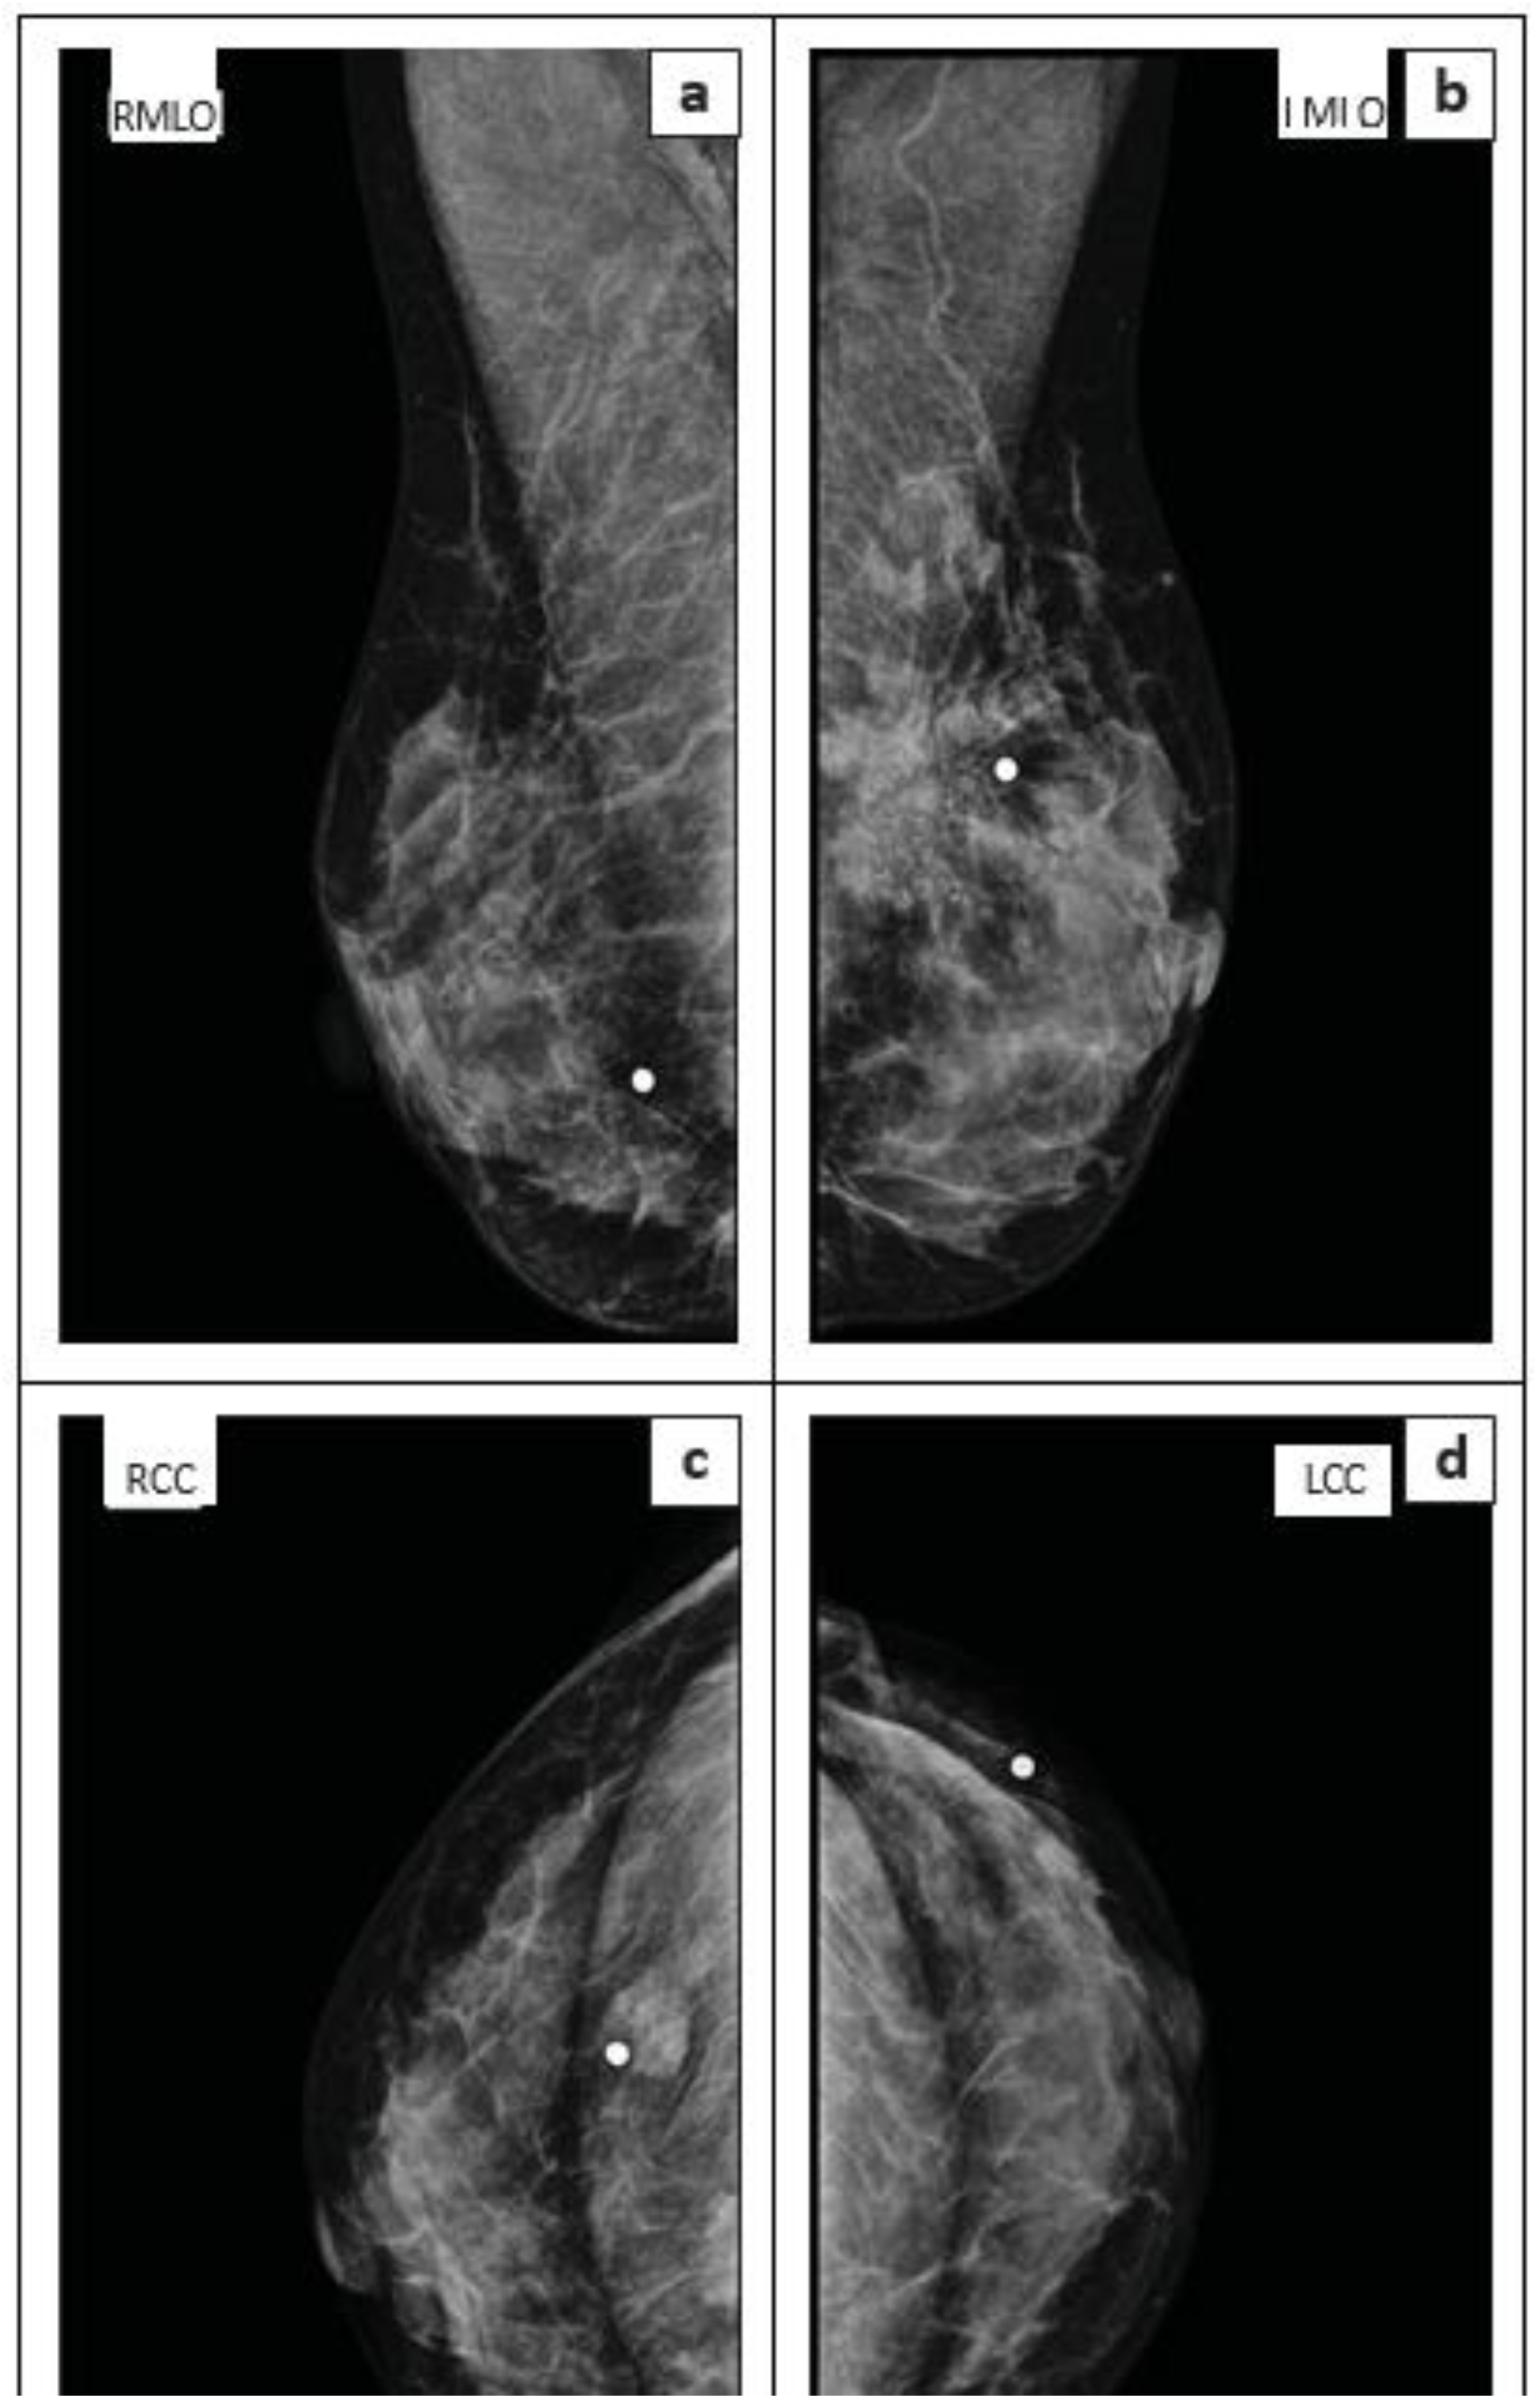

- Imaging modality: Whether the lesion was assessed using both mammography and ultrasound, or ultrasound only.

| MLO | Mediolateral Oblique |